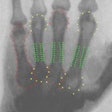

Musculoskeletal Radiology: Page 31